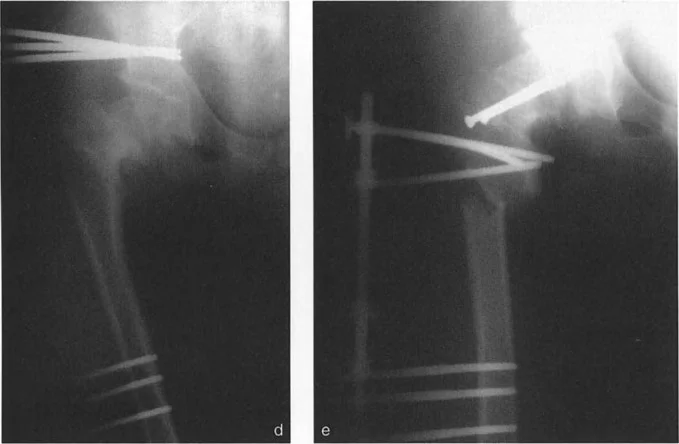

- الأشعة السينية (X-rays): هذه هي الخطوة الأولى والأكثر أهمية في تشخيص خلع الرسغ. سيتم أخذ عدة صور بالأشعة السينية من زوايا مختلفة (أمامية خلفية، جانبية، مائلة) للكشف عن أي انزياح في العظام الرسغية. في حالة خلع الرسغ المحيط بالعظم الهلالي، قد يلاحظ الأستاذ الدكتور محمد هطيف وفريقه علامات مميزة مثل "علامة الوعاء المقلوب" (Spilled Teacup Sign) في الأشعة السينية الجانبية، والتي تشير إلى انزلاق العظم الهلالي من مكانه الطبيعي، أو انزياح العظم الكبير خلف العظم الهلالي (كما هو الحال في هذه الإصابة المحددة).

- الرد المفتوح والتثبيت الداخلي (Open Reduction Internal Fixation - ORIF):

- الرد المفتوح: يتم إجراء شق جراحي (غالباً من الخلف أو الأمام أو كليهما) للوصول مباشرة إلى عظام الرسغ. يقوم الجراح بإعادة جميع العظام المخلوعة إلى مواضعها التشريحية الدقيقة تحت الرؤية المباشرة.

- التثبيت الداخلي: بعد إعادة العظام، يتم تثبيتها في مكانها باستخدام أدوات جراحية دقيقة مثل:

- أسلاك كيرشنر (K-wires): أسلاك رفيعة من الفولاذ المقاوم للصدأ يتم إدخالها عبر العظام لتثبيتها ببعضها البعض وبالعظم الهلالي.

- المسامير والصفائح المعدنية (Screws and Plates): في بعض الحالات، خاصة إذا كانت هناك كسور مصاحبة أو لتعزيز الاستقرار، قد تستخدم مسامير صغيرة وصفائح معدنية لتثبيت العظام.

- إصلاح أو إعادة بناء الأربطة: نظراً لأن تمزق الأربطة هو السبب الرئيسي للخلع، فإن الجراح يقوم بإصلاح الأربطة الممزقة قدر الإمكان. في الحالات الشديدة أو المزمنة، قد يتطلب الأمر إعادة بناء الأربطة باستخدام طعوم من أوتار المريض نفسه أو من متبرع.